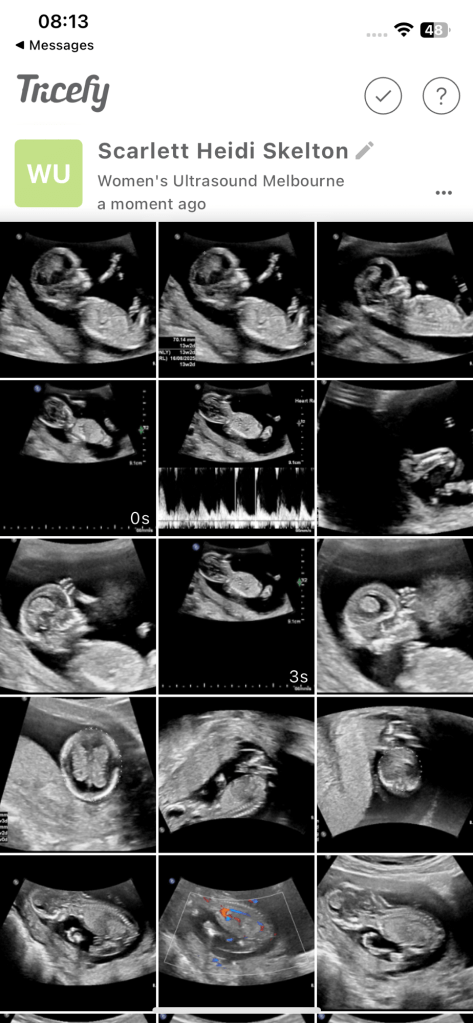

Die erste Woche war ich im Schock. So viele Pläne mussten umgedacht werden, von null auf 100 veränderte sich gefühlt alles. Was sehr fest half, war, dass Harry sich soooooooooo fest freute. Ab der Sekunde 1, in der er erfuhr, dass ich schwanger bin, transformierte Harry zu einem Superhero. Er kocht mir ein bis drei Menus pro Tag, weil ich immer hungrig bin, und organisiert ganz fleissig Babykleider, Schwangerschaftskleider, Möbel fürs Babygirl-Zimmer und alles sonst, was es braucht. Währenddessen vegetiere ich, wann immer möglich, auf dem Sofa, idealerweise mit eiskaltem Wasser und Crackers. Die Hitze ist nicht mein Freund in diesem Jahr. Am liebsten bin ich im kalten Wasser oder im heruntergekühlten Schlafzimmer. Ich fand in der 4. Woche heraus, dass ich schwanger bin. Bereits 4 Wochen? Fragte ich mich. Heute bin ich in der Woche 18 Tag 1 angekommen. Noch 22 Wochen. Bald Halbzeit. Das erste Trimester (Woche 0-13, aber besonders so Woche 10-13) (so viele neue Wörter) war so mittel cool. Es war mir eigentlich immer schlecht, ich habe am liebsten nur Brot und Crackers gegessen, ich war müde und unternommen habe ich nur so viel wie notwendig. Besonders streng waren die Wochen 10-13, als die Ferien vorbei waren und ich wieder arbeiten musste. Das war so streng. Am Ende der ersten Arbeitswoche hatte ich eine Mini-Krise, wie dies zu schaffen ist. Doch mit jeder Woche sind die Schwangerschaftssymptome ein wenig weniger geworden und ich habe mich wieder an den Schulalltag gewohnt. Aller Anfang ist schwer. Ich finde es noch immer eine unglaubliche Leistung, als Frau 100 % zu arbeiten und gleichzeitig schwanger zu sein. Nach der Arbeit gibt es nicht mehr viel ausser essen und schlafen, wenn ich ehrlich mit mir selbst bin. Nun. In Zeiten, in denen mich das frustriert, denke ich daran, dass ich ganz bestimmt nur zweimal im Leben schwanger sein werde und es eine Phase ist, die auch wieder vorübergeht. Zudem ist es auch magisch. Ein kleines Mädchen wächst in mir heran. Ich freue mich bereits jetzt auf all das Chaos, das sie anrichten wird, dass wir eine kleine Mini Version von Harry und mir in unserem kleinen glücklichen Leben willkommen heissen zu dürfen und das Leben mit ihr zu teilen. Was auch grossartig ist, dass sie gesund ist. Bei jedem Ultraschall (bis jetzt 2) und Bluttest (einmal) bekommen wir immer super Werte, das macht die Schwangerschaft sehr positiv. Ich bin zudem sehr froh, ist nun das Risiko einer Fehlgeburt, mit dem Ende der 13. Woche, sehr, gering. Bis zur 13. Woche ist es irgendwie komisch. Ich freute mich so sehr, doch traute mich auch nicht, mich zu fest zu freuen, weil was, wenn… Nun, das ist nun hinter mir und wir schreiten Vollgas in dieses neue Kapitel voller Babypoo und Kindergeschrei. Ich freue mich sehr, wirklich sehr. Auch darauf, Harry als Papa zu erleben. Harry wird der beste Papa überhaupt.

Nach Tasmanien fand der erste Ultraschall statt, wir dachten, dass wir in der 8. Woche waren. Doch die Frauenärztin bemerkte, dass dieses Baby bereits 10 Wochen alt sein musste. Hervorragend – 2 Wochen weniger Schwangerschaft.